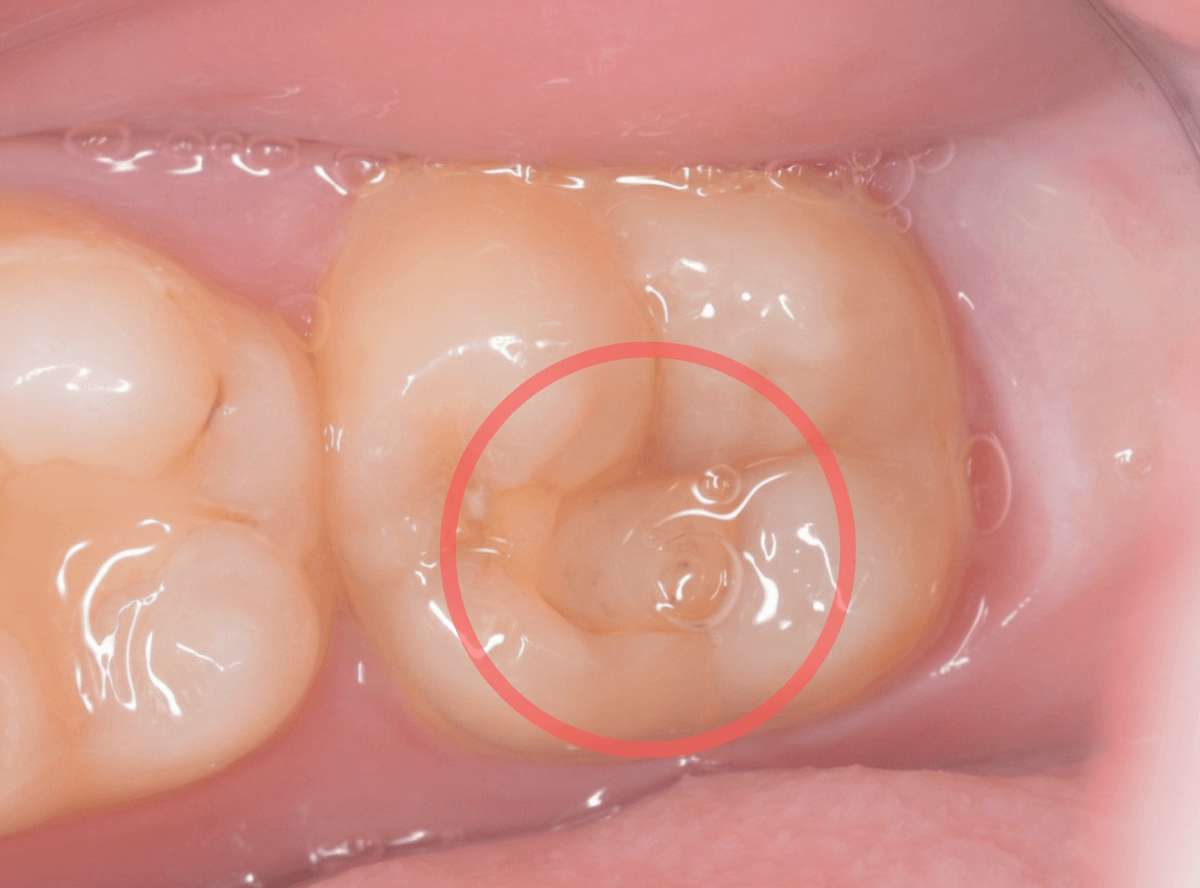

Case.12 検診で見つかった、インレーの下の深い虫歯

検診目的で来院された患者さんです。

特に気になるところもなかったですが、検査をすると、お口の中の色々な部分に虫歯が見つかりました。

その中の一か所、上の奥歯のインレーの下の虫歯です。

見た目だけでははっきりわかりませんでしたが、レントゲン写真で確認すると、インレーの下で虫歯になっているのがわかります。